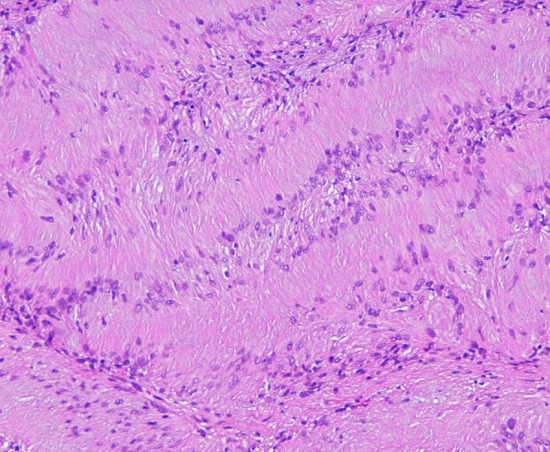

細胞核が円状に並んだ形態で、いわゆるVerocay bodyと呼ばれる所見(矢印)。 HE x200.

紡錐型の核を有する腫瘍細胞で構成されます。左側の写真のように,古典的病理所見として,束状 fascicular に配列する密な組織である Antoni A Typeと網状 reticular で疎な組織である Antoni B Typeが混在するパターンを示します。神経鞘腫では多少の核の異型性がみられても悪性像とはいえません。嚢胞を形成したり,時には毛細血管拡張 simple hemangioma を思わせるような著明な血管の増生があり腫瘍内出血をきたすことがあります。